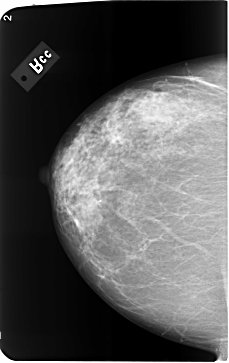

B_3493_1.RIGHT_CC

RIGHT_CC LINES 5808 PIXELS_PER_LINE 3664 BITS_PER_PIXEL 12 RESOLUTION 50 NON_OVERLAY